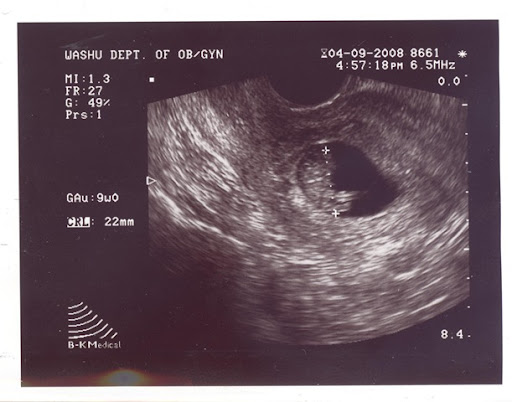

Otra de las razones para comprar coche nuevo, más grande y más seguro, es que, como casi todos ya sabeís, vamos a ampliar la familia.

Leticia está ahora (27 de abril) embarazada de 11 semanas. Por ahora todo va bien. Lo esperamos para la semana del 11 de noviembre, así que será ciudadano/a americano. Por ahora no sabemos mucho más. Aún no sabemos el sexo de bebe. El nombre tampoco está decidido, pero estamos abiertos a sugerencias, ya sabeís, las podeís dejar en los comentarios.